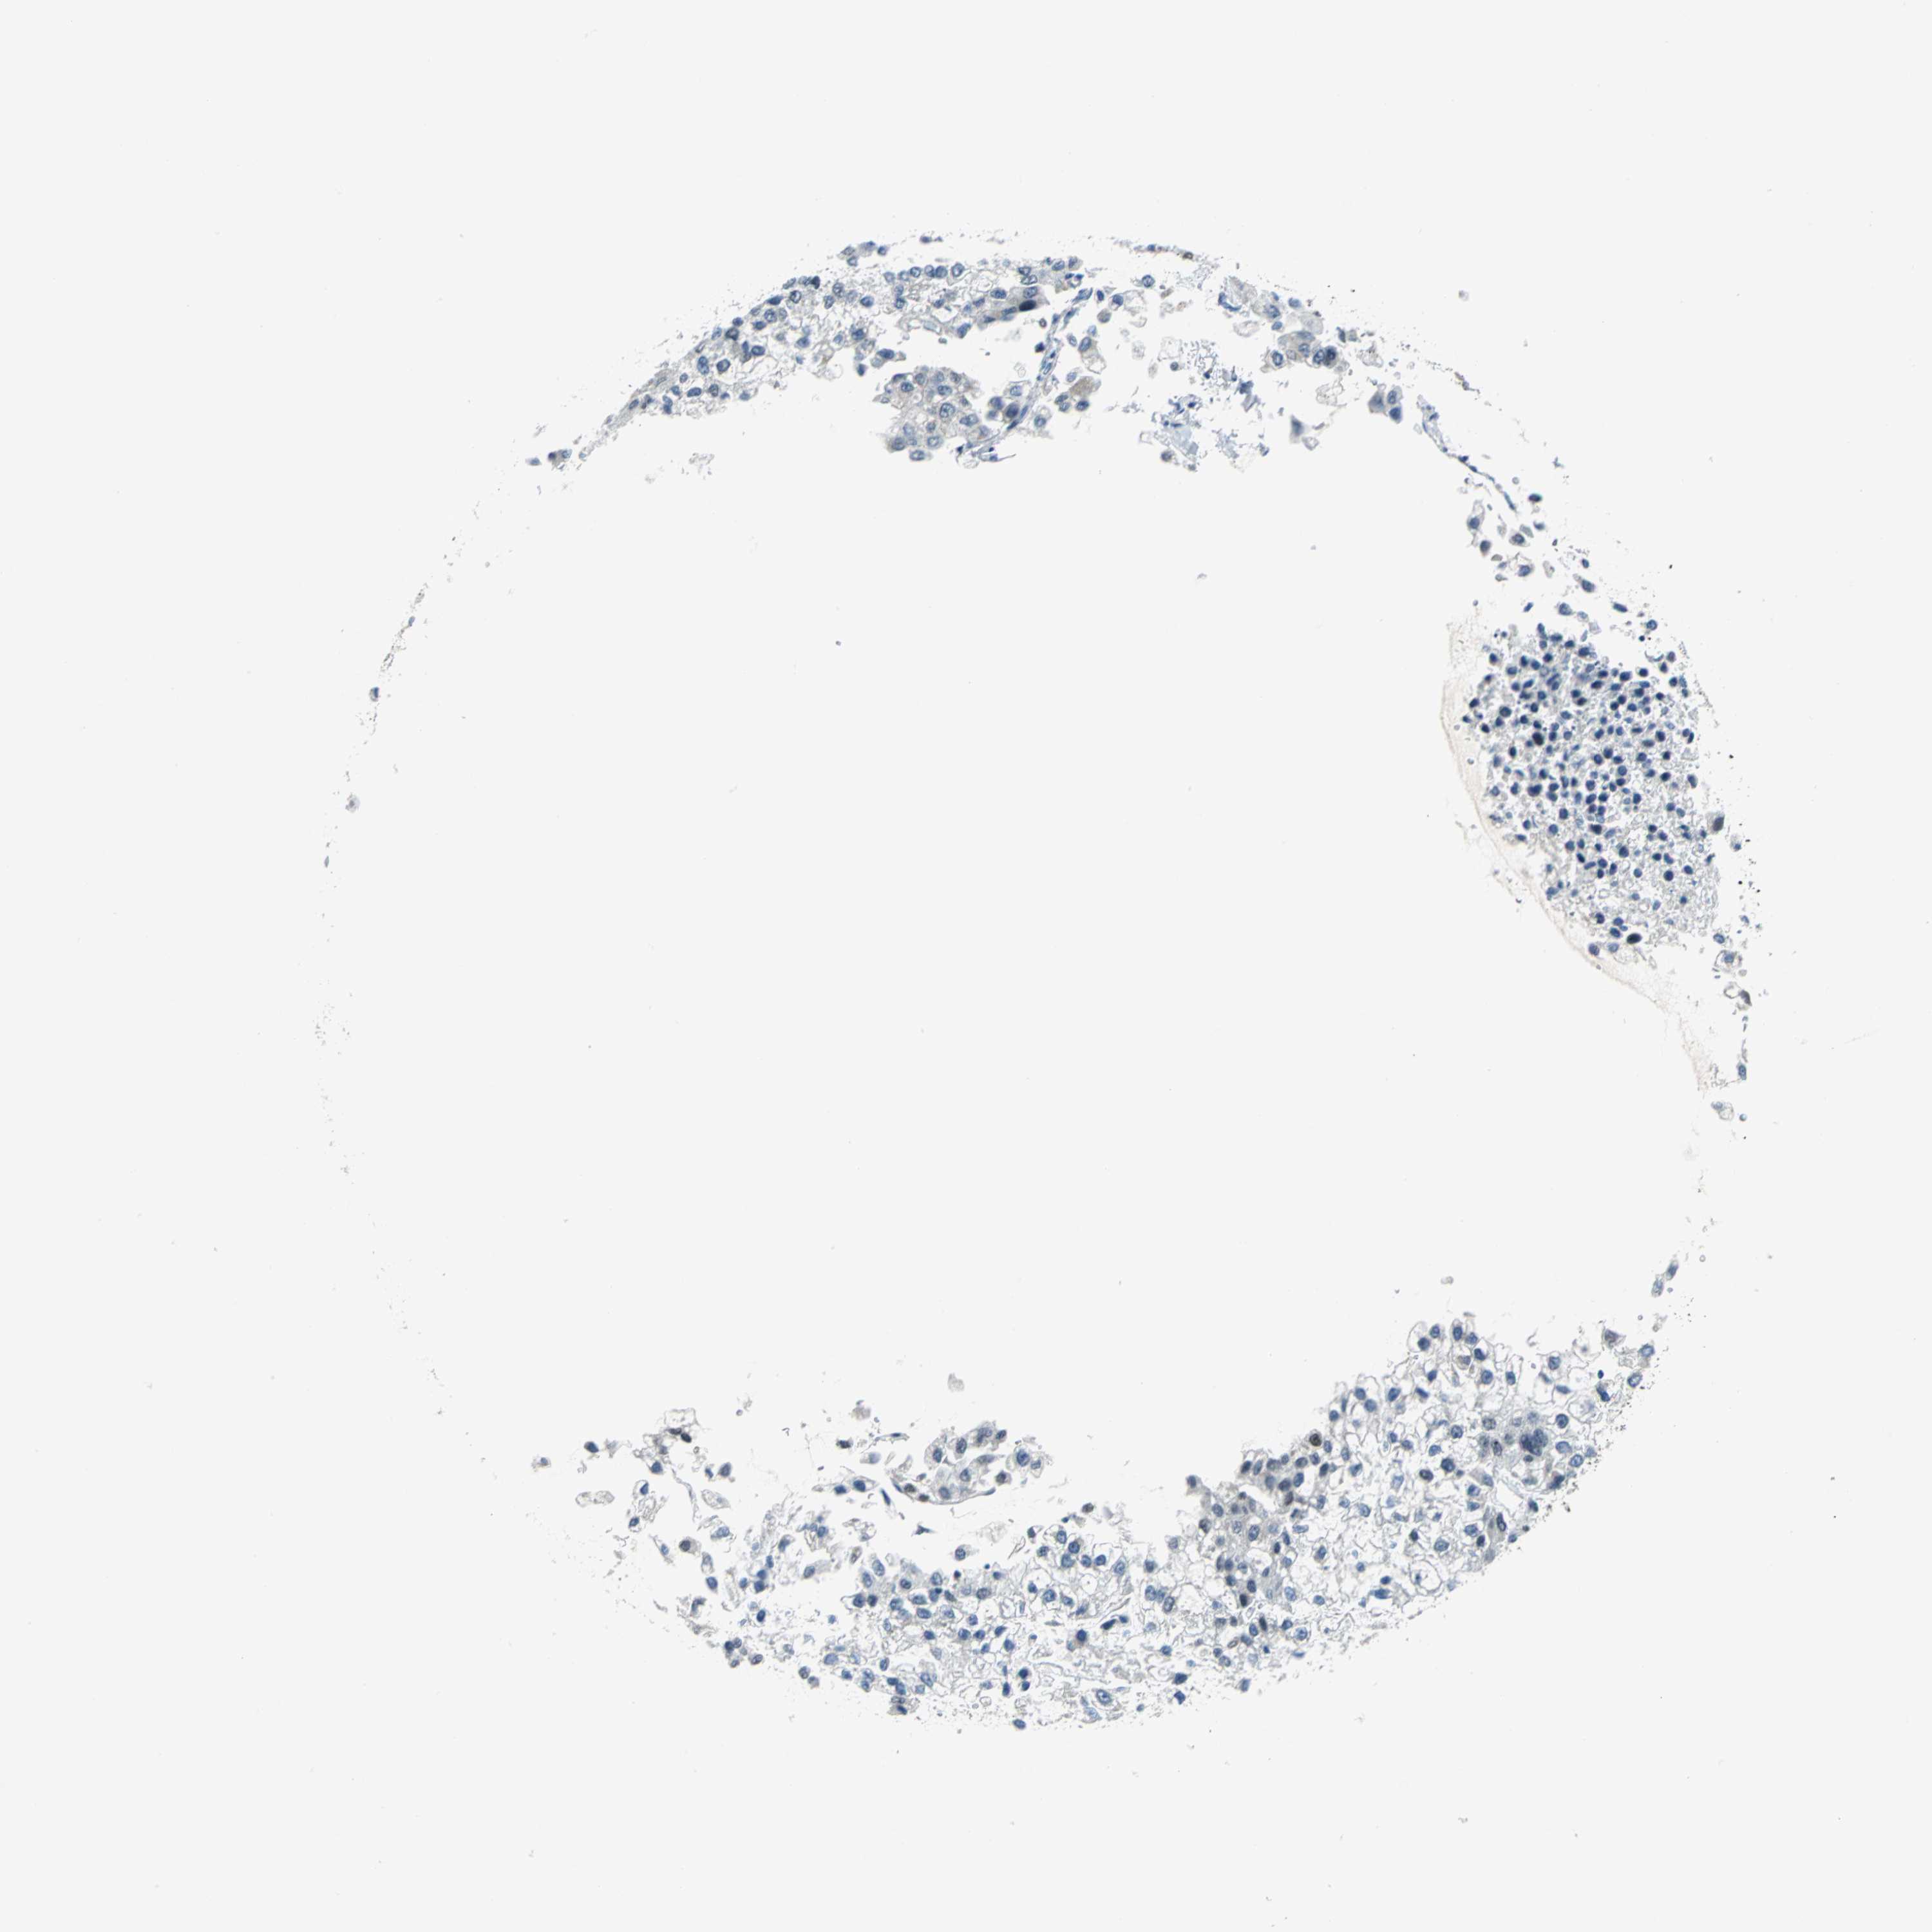

LIVER CANCER - Protein expressioni

A mouse-over function shows sample information and annotation data. Click on an image to view it in a full screen mode. Samples can be filtered based on level of antibody staining by selecting one or several of the following categories: high, medium, low and not detected. The assay and annotation is described here.

Note that samples used for immunohistochemistry by the Human Protein Atlas do not correspond to samples in the TCGA dataset.

Antibody stainingi

Antibody staining in the annotated cell types in the current human tissue is reported as not detected, low, medium, or high, based on conventional immunohistochemistry profiling in selected tissues. This score is based on the combination of the staining intensity and fraction of stained cells.

Each image is clickable and will lead to virtual microscopy that enables deeper exploration of all samples and also displays staining intensity scores, fraction scores and subcellular localization as well as patient and tissue information for each sample.

Antibody HPA004873

Antibody CAB004497

Staining

High

Medium

Low

Not detected

Intensity

Strong

Moderate

Weak

Negative

Quantity

>75%

75%-25%

<25%

None

Location

Nuclear

Cytoplasmic/membranous

Cytoplasmic/membranous,nuclear

Cholangiocarcinoma

Carcinoma, Hepatocellular, NOS